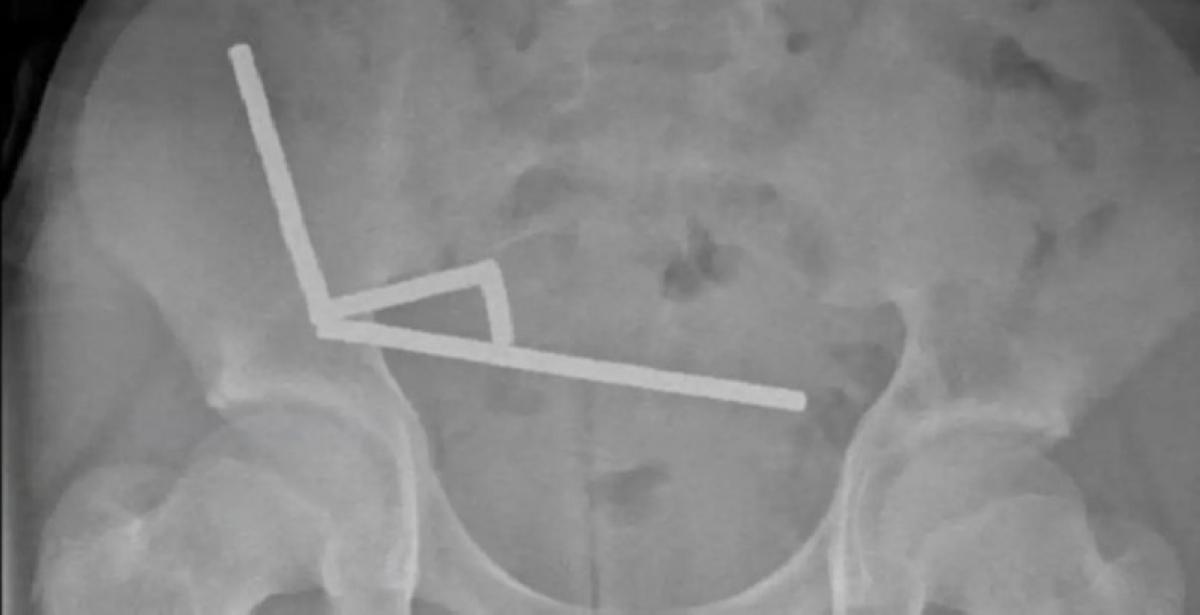

حادثة غريبة في نيوزيلندا أعادت تسليط الضوء على مخاطر الألعاب المغناطيسية، حيث خضع صبي يبلغ من العمر 13 عامًا لعملية طارئة لاستخراج حوالي 200 مغناطيس صغير من أمعائه. نُقل الصبي إلى مستشفى “تاورانغا” وهو يعاني من آلام شديدة في البطن، ليكتشف الأطباء لاحقًا وجود المغناطيسات التي تسببت في انسداد داخلي وتسرب في الأنسجة.

الجراحون أشاروا إلى أن المغناطيسات التصقت بجدران الأمعاء، مما أدى إلى تقليل تدفق الدم وتمزق أجزاء من الجهاز الهضمي. رغم خطورة حالته، تمكن الفريق الطبي من إنقاذه بعد استئصال جزء من الأمعاء المتضررة. أعلن الأطباء أن الطفل تعافى بعد 8 أيام، لكن الحادث دفع الجهات الصحية في نيوزيلندا لتجديد التحذير من خطورة تلك الألعاب.